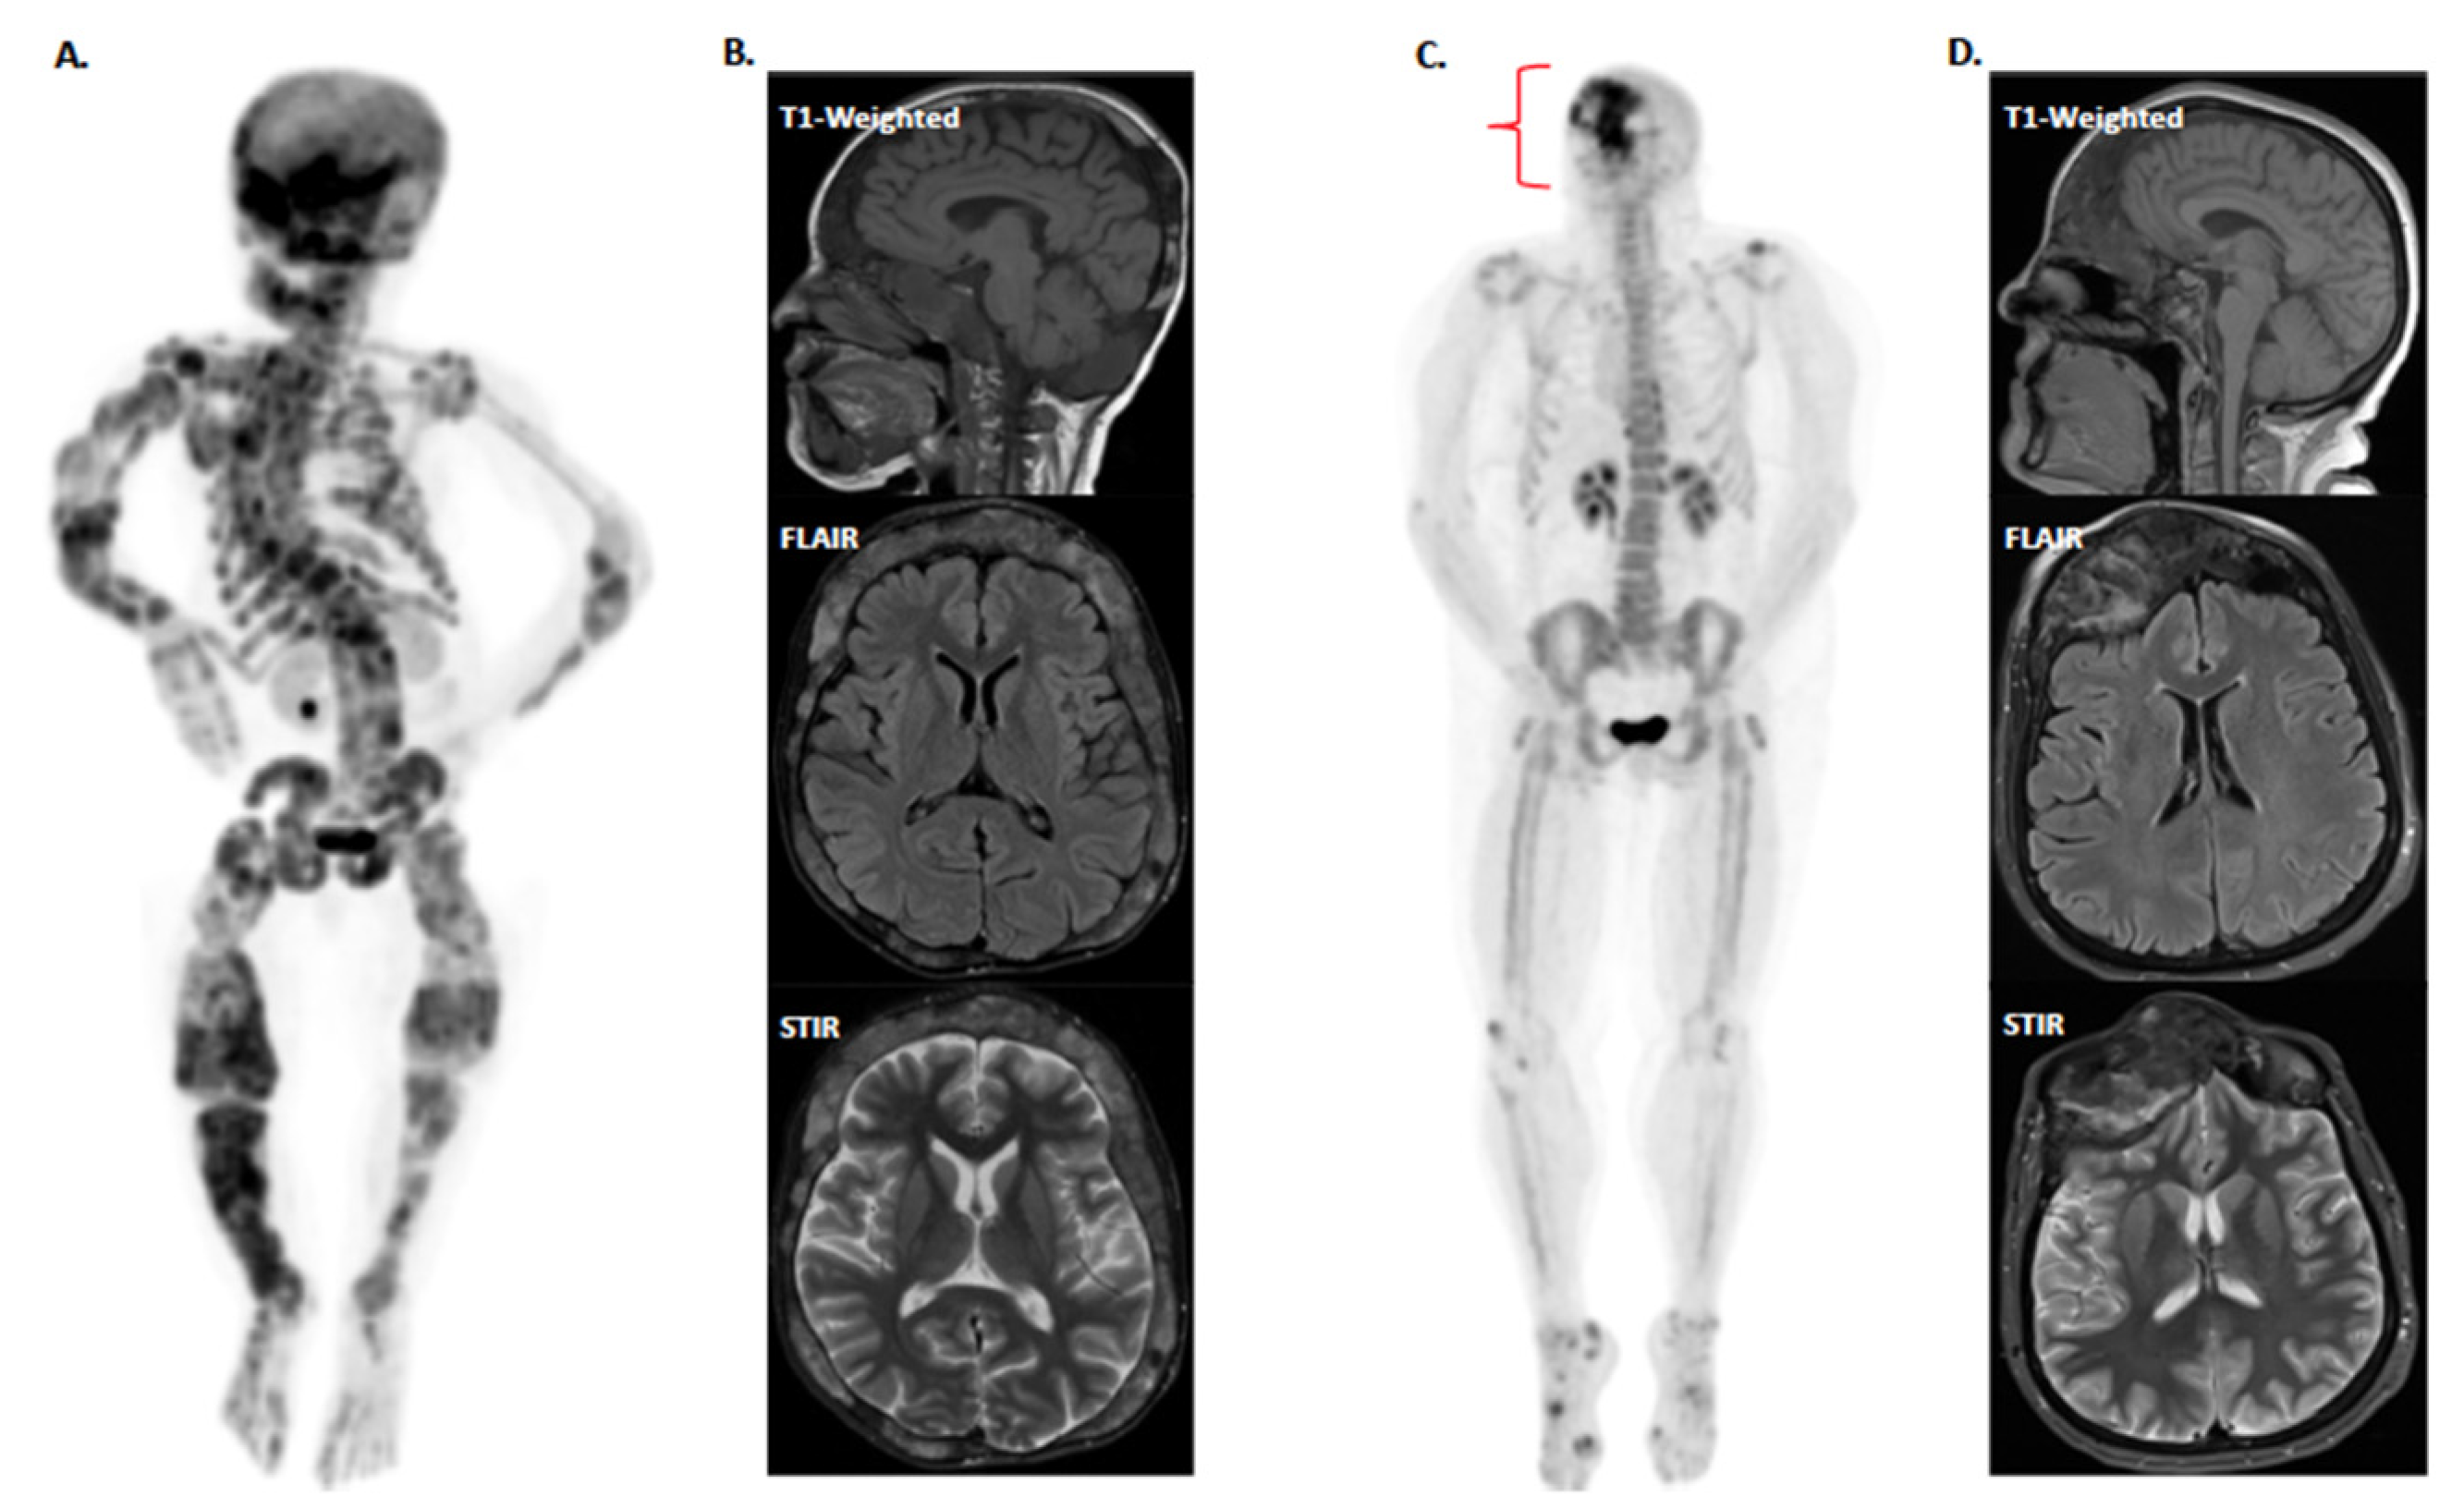

2. Therapeutics for Treating Pain in FD/MAS

3. Experiences with Pain in Individual FD/MAS Cases